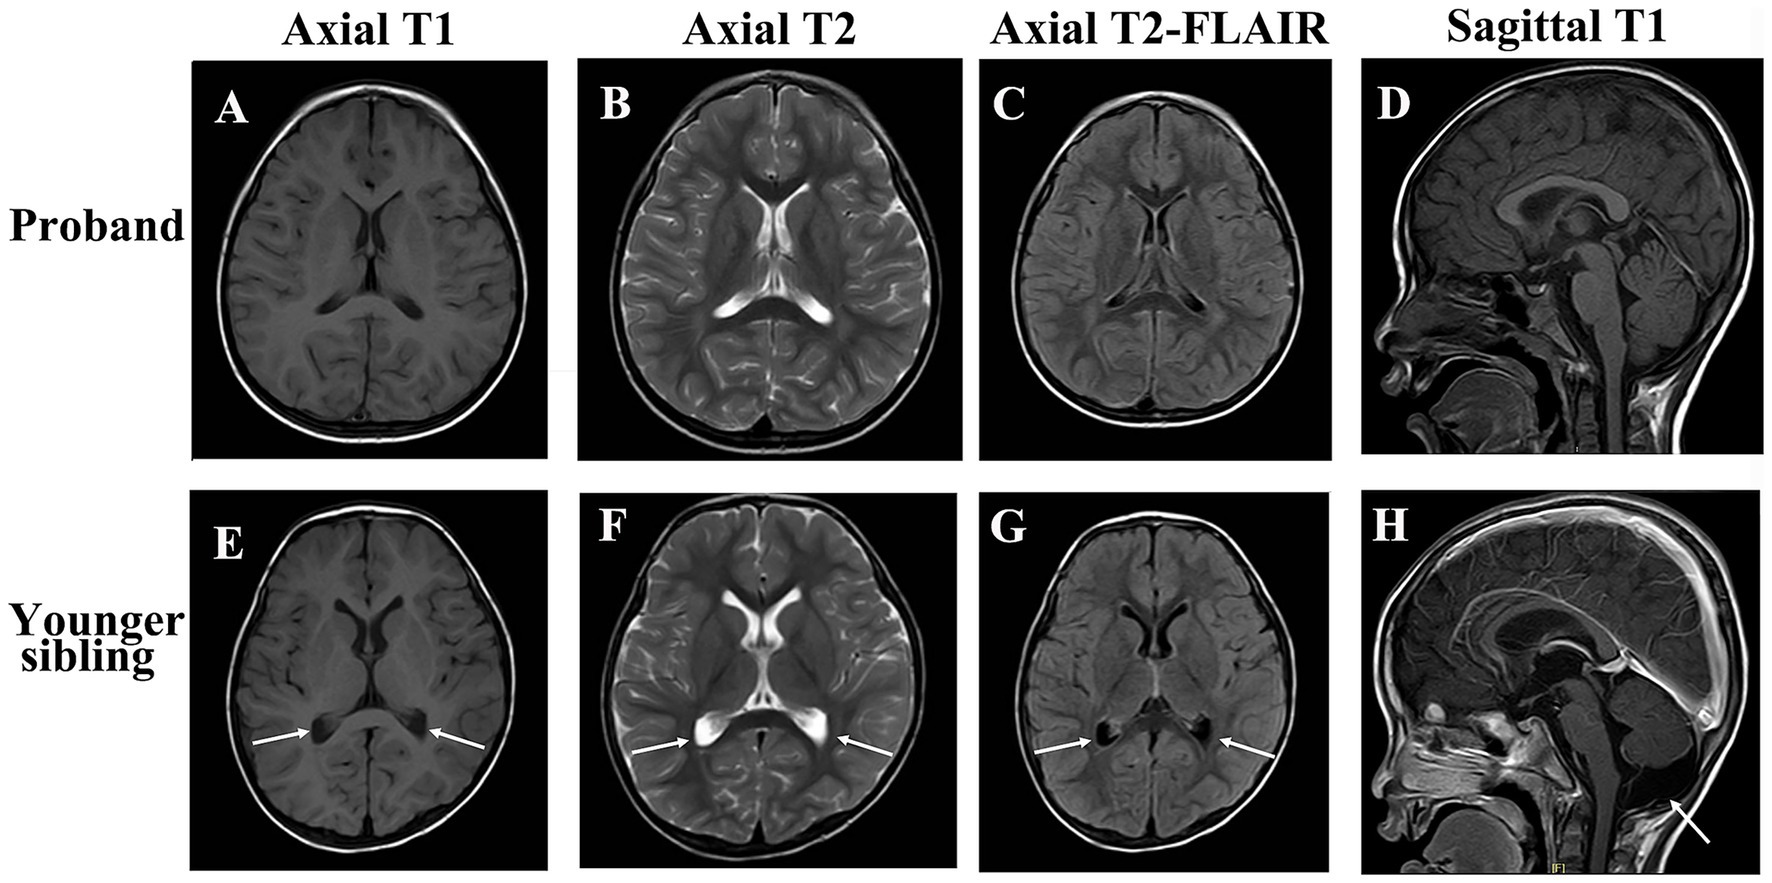

Brain MRI of the patients. Brain MRI of the proband: (A) Axial T1-weighted image; (B) Axial T2-weighted image; (C) Axial T2-weighted FLAIR image. (D) Sagittal T1-weighted No structural abnormalities were observed. Brain MRI of the proband’s younger brother: (E) Axial T1-weighted image; (F) Axial T2-weighted image; (G) Axial T2-weighted FLAIR image. (H) H Sagittal T1 post-contrast; Mild lateral ventricular enlargement and a prominent cisterna magna were noted. Arrowheads in (E–G) indicate mild lateral ventricular enlargement; the arrow in (H) highlights a prominent cisterna magna.

Diagnostic investigations were obtained at different time points during the disease course. Whole-exome sequencing identified compound heterozygous variants in KCTD7: c.334C > T (p.Arg112Cys) in exon 3, inherited from her father, and c.640C > T (p.Arg214Trp) in exon 4, inherited from her mother. The variants were subsequently confirmed by Sanger sequencing in both parents. The c.334C > T (p.Arg112Cys) variant had previously been reported as a homozygous variant in a patient with KCTD7-related progressive myoclonic epilepsy (Yoganathan et al., 2024). According to ClinVar, this variant was classified as uncertain significance (VUS) under record RCV001297140.8 (last evaluated June 22, 2022), but was subsequently reclassified as likely pathogenic (LP) under record RCV001562390.4 (last evaluated March 5, 2024). The c.640C > T (p.Arg214Trp) variant, inherited from the mother, has not been reported in the literature. However, an entry for this variant was submitted to ClinVar under record RCV001065036.8, where it is currently classified as a variant of uncertain significance (VUS) (last evaluated February 8, 2022). This variant affects a highly conserved residue and is predicted to be deleterious by multiple in silico algorithms. Both variants are rare (minor allele frequency <0.0005 in gnomAD). Sanger sequencing confirmed segregation of the variants within the family (Figure 1). Protein structural modeling using PyMOL and I-Mutant 3.0 demonstrated that both missense variants are likely to disrupt local residue interactions and reduce protein stability, supporting their pathogenic potential (Figure 2A). Multiple sequence alignment showed that the affected residues are highly conserved across vertebrate species, including Homo sapiens, Pan troglodytes, Mus musculus, Rattus norvegicus, Canis familiaris, Gallus gallus, Xenopus tropicalis, and Danio rerio. The variant sites are highlighted in red, and shading intensity reflects the degree of residue conservation (Figures 2B,C). According to American College of Medical Genetics and Genomics (ACMG) criteria, the c.334C > T variant can be classified as likely pathogenic, supported by rarity in population databases (PM2: absent or extremely rare in population databases), deleterious computational predictions (PP3: multiple in silico algorithms support a damaging effect), and segregation evidence in the family (PP1: cosegregation with disease in affected family members), while the c.640C > T variant remains a variant of VUS. Laboratory investigations were unremarkable, including blood lead level, cerebrospinal fluid (CSF) routine and biochemistry, autoimmune encephalitis antibody panel (NMDAR, AMPAR1/2, LGI1, CASPR2, GABABR, IgLON5, DPPX, GAD65, GlyRα1, mGluR5, and D2R in both serum and CSF), cerebellar ataxia–related antibodies (GAD65, Homer3, ARHGAP26, ATP1A3, CARP VIII, NCDN, GluRδ2, CASPR2, PCA2, Yo, mGluR1/2/8, and KLHL11 in serum and CSF), and paraneoplastic neuronal antibody panel (Hu, Ri, CV2, Ma1/2, amphiphysin, GAD65, Tr, Zic4, PKCγ, and SOX1 in CSF). Brain and spinal magnetic resonance imaging (MRI) were normal (Figures 3A–D). Video EEG demonstrated generalized background slowing with frequent frontally predominant spikes, slow waves, and spike-slow wave discharges during both wakefulness and sleep. Cognitive evaluation indicated intellectual disability (full-scale IQ 61; verbal IQ 58; performance IQ 69) and moderate social adaptation impairment.

Upon admission to our institution, ophthalmologic evaluation showed right eye visual acuity of 0.6 and left eye refraction of −1.25/−0.25 × 1.18. A clinical phenotype consistent with PME was observed, characterized by myoclonic seizures, ataxia, and neurodevelopmental regression, although generalized tonic–clonic seizures were not clearly documented. Brain MRI demonstrated mild lateral ventricular enlargement and a prominent cisterna magna (Figure 3E–H). Treatment included intravenous methylprednisolone (20 mg/kg/day, followed by gradual oral taper), intravenous immunoglobulin (initial dose 2 g/kg over 4 days), and continued antiepileptic therapy with valproic acid and clonazepam. Levetiracetam was subsequently added and titrated to 40 mg/kg/day. Repeat video EEG demonstrated background slowing with continuous right hemispheric spike-slow wave and polyspike-slow wave discharges, with a spike–wave index of 75–85%.

Both siblings presented with ataxia, cognitive decline, and myoclonic seizures. EEG showed multifocal epileptiform discharges, background slowing, and sleep-activated discharges including ESES with spike–wave indices of 85–95%. MRI findings were unremarkable, which aligns with previous literature indicating nonspecific or absent MRI abnormalities in KCTD7-related PME. These clinical and electroencephalographic findings support the role of KCTD7 dysfunction in cortical hyperexcitability, likely mediated through potassium channel dysregulation and impaired autophagy support the role of KCTD7 dysfunction in cortical hyperexcitability, likely through potassium channel dysregulation and impaired autophagy (Yoganathan et al., 2024).